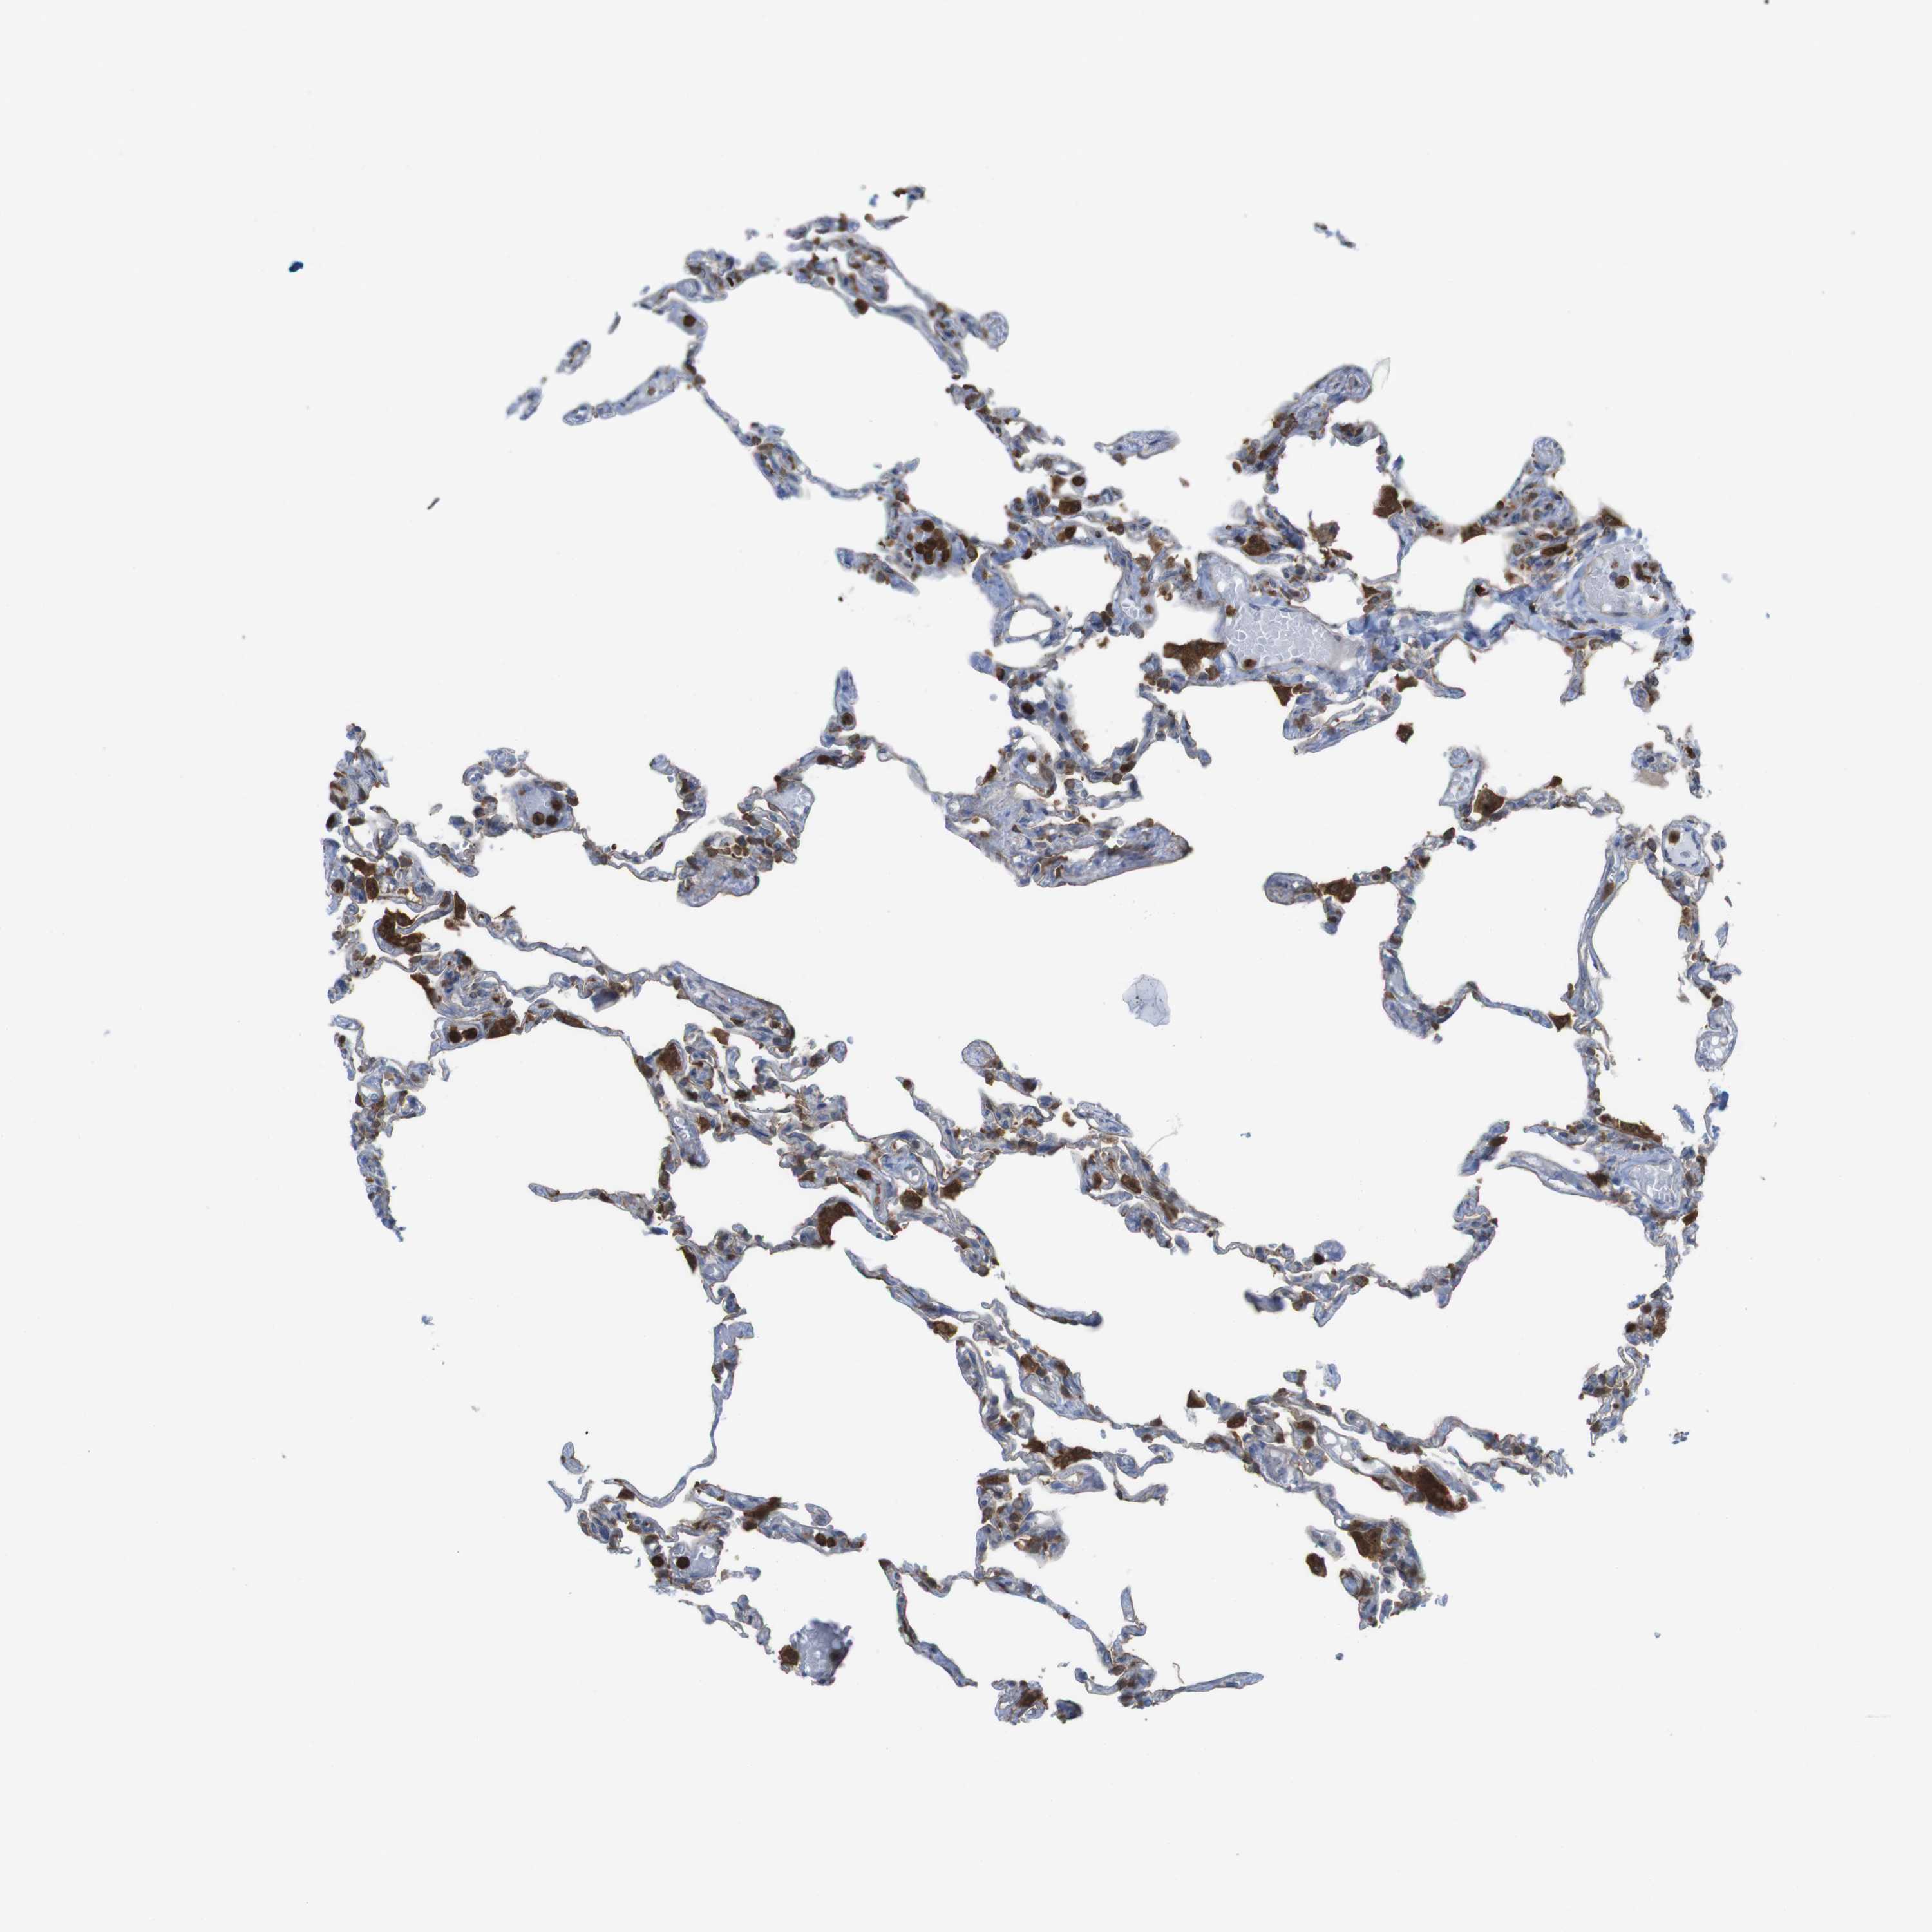

LUNG - Antibody stainingi

Antibody staining in the annotated cell types in the current human tissue is reported as not detected, low, medium, or high, based on conventional immunohistochemistry profiling in selected tissues. This score is based on the combination of the staining intensity and fraction of stained cells. Each image is clickable and will lead to virtual microscopy that enables deeper exploration of all samples and also displays staining intensity scores, fraction scores and subcellular localization as well as patient and tissue information for each sample.

Antibody HPA001863Antibody HPA001890Antibody CAB010469Antibody CAB013225

Alveolar cells HighMediumLow-

Alveolar cells type I ---Medium

Alveolar cells type II ---Medium

Endothelial cells ---Not detected

Macrophages HighHighHighHigh